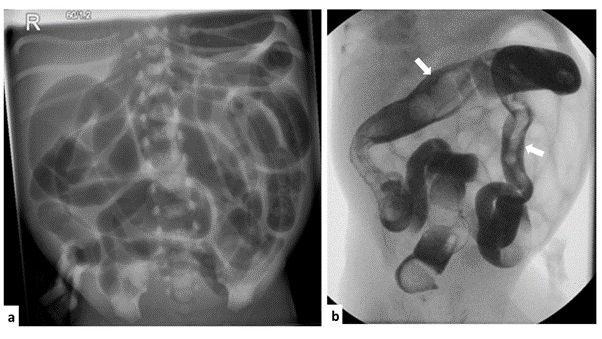

Plain radiographs typically show features of lower intestinal obstruction with multiple dilated loops. The gas pattern is usually generalised and symmetrical with no air-fluid levels as opposed to features seen in mechanical obstruction (Fig. 1). Pneumatosis, fixed bowel loop, and portal gas which are characteristic of NEC are absent. Clinical findings and plain x-ray are often sufficient to make a diagnosis and institute management especially in the ELBW cohort that may require cardio-respiratory support.[12]

Contrast enema is both diagnostic and therapeutic. Meconium plugs are demonstrated as filling defects in the non-distended colon and terminal ileum if contrast refluxes through the ileo-caecal valve (Fig. 1). Micro/unused colon with associated collapsed distal ileum is seen but this may not be well demonstrated if rectal washouts have been commenced before contrast study. Contrast enema also helps to exclude other causes of bowel obstruction like atresia and Hirschsprung’s disease.

(a) Plain abdominal radiograph of preterm with FIOP showing generalised bowel distension. (b) Meconium plugs, shown as filling defects (arrows) in the non-distended colon and terminal ileum are seen on the contrast enema study